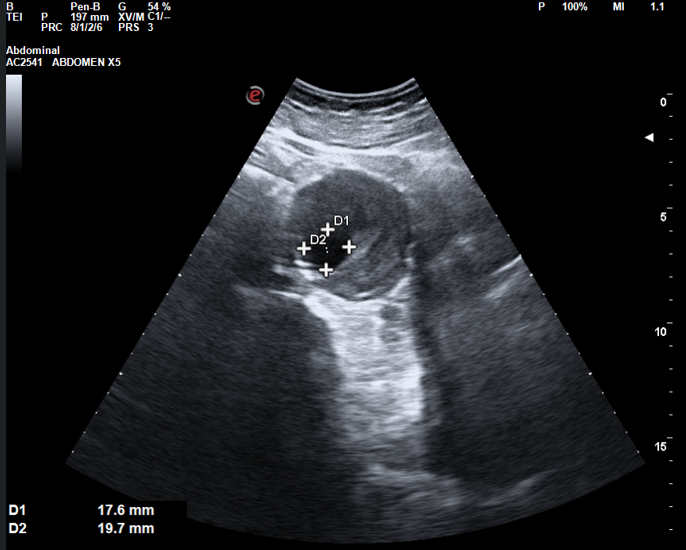

Ecografía abdominal: Hígado de tamaño y ecogenicidad normal, sin dilatación de vía biliar. Vesícula de pared fina con litiasis única en su interior. Páncreas de aspecto normal. Ambos riñones de tamaño normal, con buena diferenciación corticomedular, sin dilatación de vía urinaria ni presencia de litiasis. Bazo de tamaño y ecogenicidad normal. En el rastreo de abdomen inferior se descubre incidentalmente aorta abdominal con aumento de su diámetro (5,6 x 5,3 cm), se aprecia imagen de engrosamiento de pared compatible con trombo intramural y luz permeable de 1,7 x 1,9 cm.